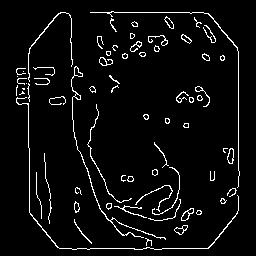

(a) Refer to caption Refer to caption Refer to caption Refer to caption Refer to caption Refer to caption

(b) Refer to caption Refer to caption Refer to caption Refer to caption Refer to caption Refer to caption

(c) Refer to caption Refer to caption Refer to caption Refer to caption Refer to caption Refer to caption

(d) Refer to caption Refer to caption Refer to caption Refer to caption Refer to caption Refer to caption

(e) Refer to caption Refer to caption Refer to caption Refer to caption Refer to caption Refer to caption

(f) Refer to caption Refer to caption Refer to caption Refer to caption Refer to caption Refer to caption

(g) Refer to caption Refer to caption Refer to caption Refer to caption Refer to caption Refer to caption

(h) Refer to caption Refer to caption Refer to caption Refer to caption Refer to caption Refer to caption

Figure 3: Sample data used and generated in the different steps of PolypConnect pipeline. (a) - real polyp images, (b) - manually annotated polyp masks, (c) - randomly selected colon images used as input to the final step of PolypConnect, (d) - extracted edge images of row c. (e) - extracted edge images of polyp regions of row a using the masks of row b. (f) - combined edge images of row d and f. (g) - generated polyp on the images of row c using EdgeConnect. (h) - generated samples from AOTGAN.